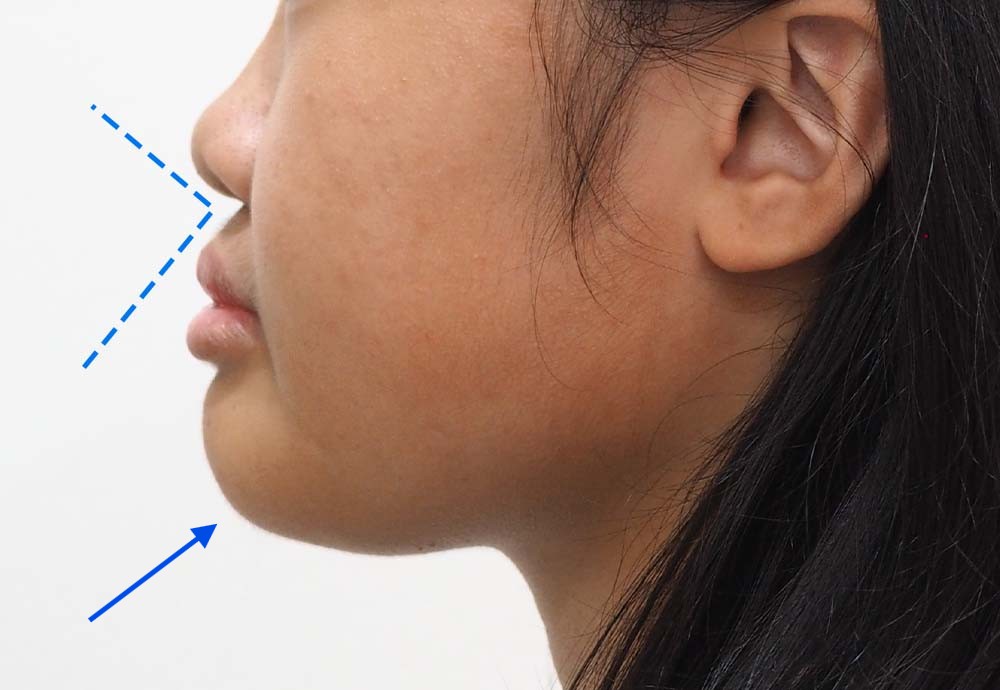

Dental Condition: Protruded side profile

In the right hands, braces can also subtly improve overall facial harmony and aesthetics (while correcting underlying jaw and tooth alignment issues).

Unlike metal braces that often rely on extraction to create space, clear aligners allow gentle arch expansion and digitally planned movement (distalization etc) to ensure the least compromise in facial profile.

Perfect if your facial profile makes you unsuitable for extraction.